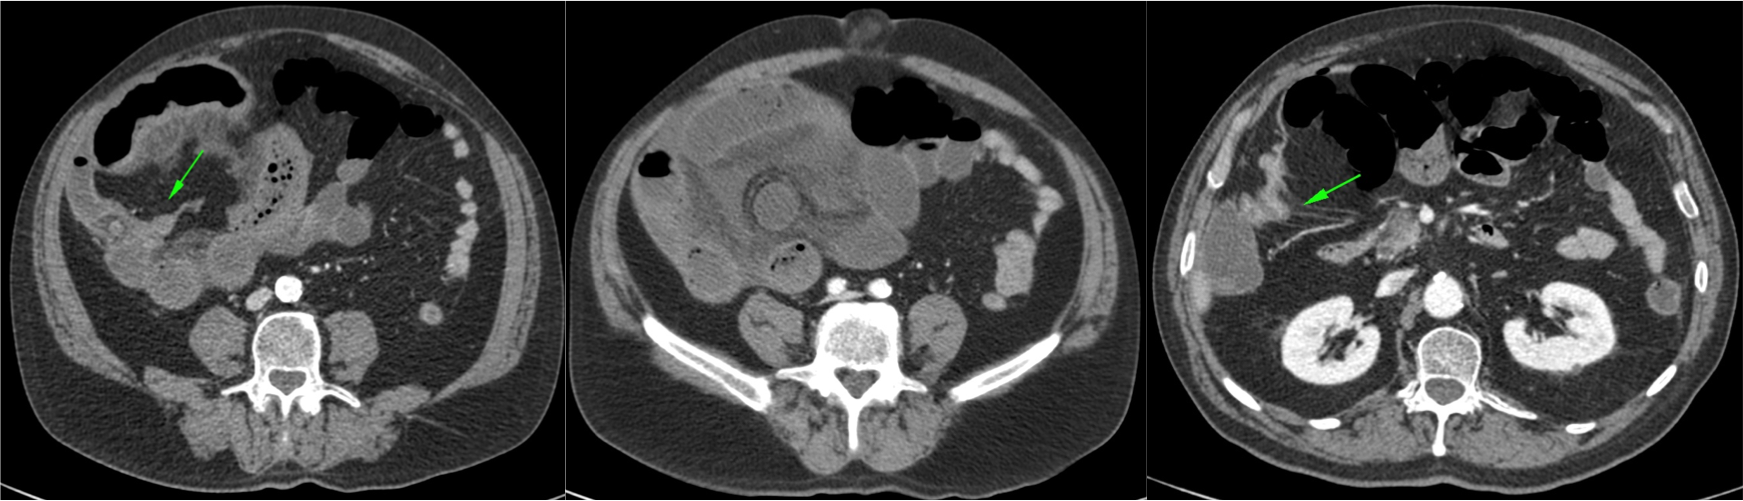

El íleo biliar se define como la obstrucción mecánica causada por la impactación en el lumen intestinal de una litiasis biliar procedente de la vesícula. Es una complicación que ocurre en el 0.3 – 0.5% de todas las colelitiasis.

Aunque su frecuencia global es baja, en pacientes ancianos no lo es tanto, llegando a constituir alrededor del 25% todas las obstruciones intestinales no estranguladas. Al igual que en la coletitiasis, es más frecuente en mujeres.

Su mortalidad varía entre el 8 -30%, llega a ser bastante alta sobre todo en ancianos con patología concomitante.

Placa simple: Triada de Rigler: Obstrucción de asas de delgado + gas en el arbol biliar + litiasis (frec en la FID); estos tres hallazgos constituyen la Triada de Rigler.

Tomografía computarizada: S y E del 93% y 100% respectivamente. Hallazgos: Dilatación por obstrucción de asas de delgado. Aerobilia. Litiasis (2 – 3 cm aprox). Hay que tener cuidado ya que muchas litiasis no están calcificadas y su densidad puede ser similar al contenido del intestino. Pueden ser multiples, por tanto hay que poner atención para que no pasen desapercibidas y evitar las recidivas. Fistulas (normalmente entre vesícula y duodeno). Neumoperitoneo (gas portal o gas mural indican peor pronóstico).

Sindrome de Bouveret: Es un tipo de íleo biliar muy proximal y poco frecuente, donde una litiasis migra a través de una fístula desde la vesícula biliar al duodeno proximal o al píloro gástrico, produciendo ahí una obstrucción.